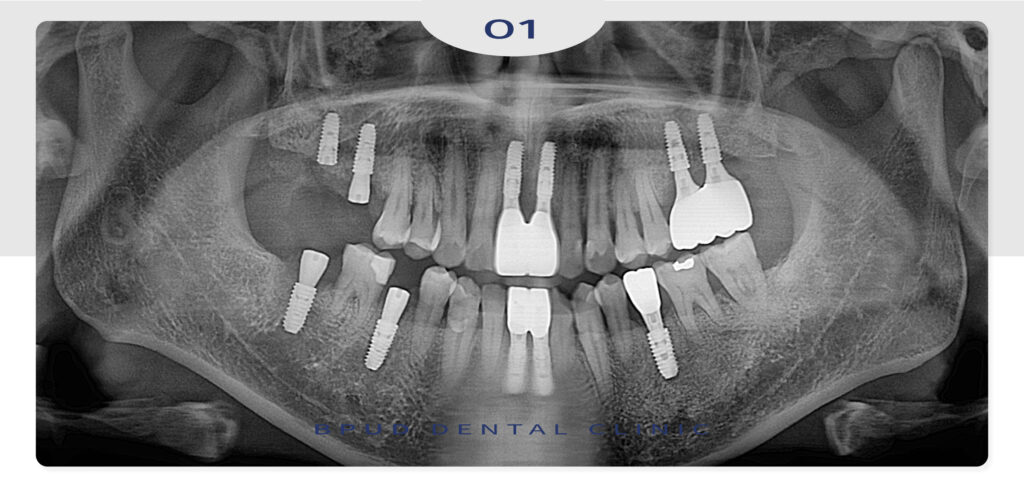

오늘은 타 치과에서 발치하고 오신

앞니 부위 뼈이식을 동반한 부평임플란트를

진행하신 환자분을 소개해 드리려고 합니다.

환자분께서는 심한 충치와 염증으로 인해

2주 전에 타원에서 위, 아래 앞니를 발치 후

지인 분의 소개로 부평유디에 내원해 주셨는데요.

이미 많은 양의 치조골이 흡수되신 상황으로

앞니 치료를 가장 먼저 우선시 하여

왼쪽 위 어금니 부위 부평임플란트까지

계획을 수립하여 진행하시기로 하였습니다.

앞니 부위도 골흡수가 많이 진행되었으나

치조골 이식을 시행하여 볼륨을 회복할

수 있도록 하였는데요.